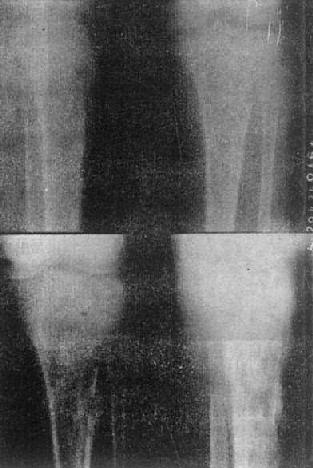

图2-1-12 胫骨慢性化脓性骨髓炎,花边状骨膜增生

图2-1-13 胫骨慢性化脓性骨髓炎

上图可见骨破坏及骨膜反应,有死骨形成。下图为半年后,死骨更为明显